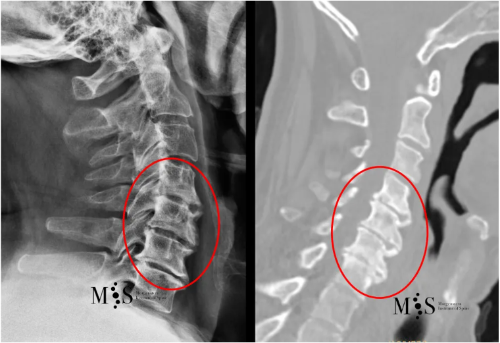

CT Scan (right) and X-ray film (left) of a cervical spine with advanced

degeneration of the cervical interbody disks (marked by a red circle).